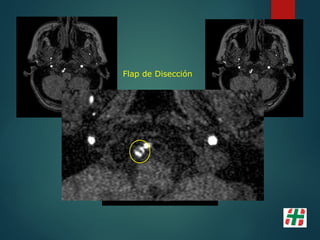

Disección Vascular

 Causa frecuente de Stroke isquémico en adultos jóvenes.

 Desgarro de la pared con formación de hematoma mural.

 Multifactorial, Trauma, infecciones, etc.

 Determinar extensión.

Mayor indicación de la secuencia TOF. Valor del crudo.

Flap de Disección

Disección Vascular  Causafrecuente de Stroke isquémico en adultos jóvenes.  Desgarro de la pared con formación de hematoma mural.  Multifactorial, Trauma, infecciones, etc.  Determinar extensión.  Mayor indicación de la secuencia TOF. Valor del crudo.